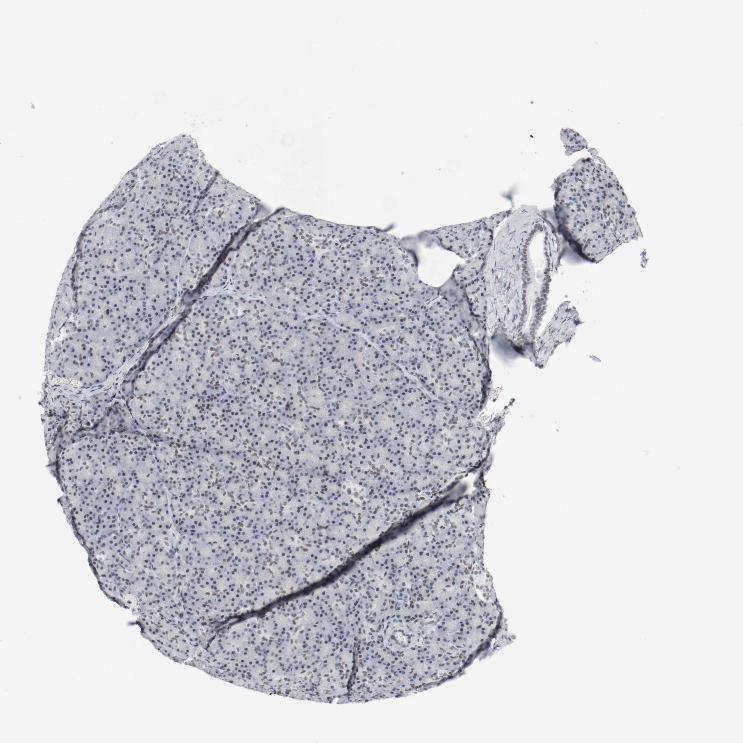

PANCREAS - Antibody stainingi

Antibody staining in the annotated cell types in the current human tissue is reported as not detected, low, medium, or high, based on conventional immunohistochemistry profiling in selected tissues. This score is based on the combination of the staining intensity and fraction of stained cells.

Each image is clickable and will lead to virtual microscopy that enables deeper exploration of all samples and also displays staining intensity scores, fraction scores and subcellular localization as well as patient and tissue information for each sample.

Antibody HPA001759Antibody CAB004318

Exocrine glandular cells MediumLow

Pancreatic endocrine cells Medium-